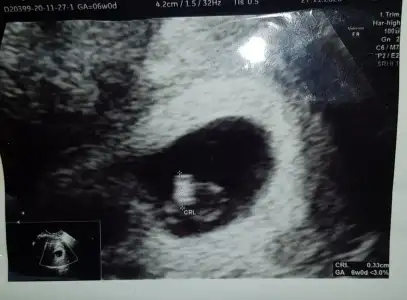

dr soylemeden siz gorun genital nub teorisi ( bebegin cinsiyeti)

Bana da bakarmısın lütfen 11+4 haftalık 🥰